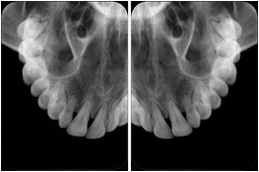

2. A patient requests cosmetic surgery to enhance their facial appearance. The case requires consultation between an orthodontist in New York and an oral surgeon in California. The cephalometric series of 2D projections constructed from a volumetric CT data set that is used for the discussion is arranged by a Structured Display for transfer between the two practitioners.

Cephalometric Series Structured Display

Figure OO-2. Cephalometric Series Structured Display